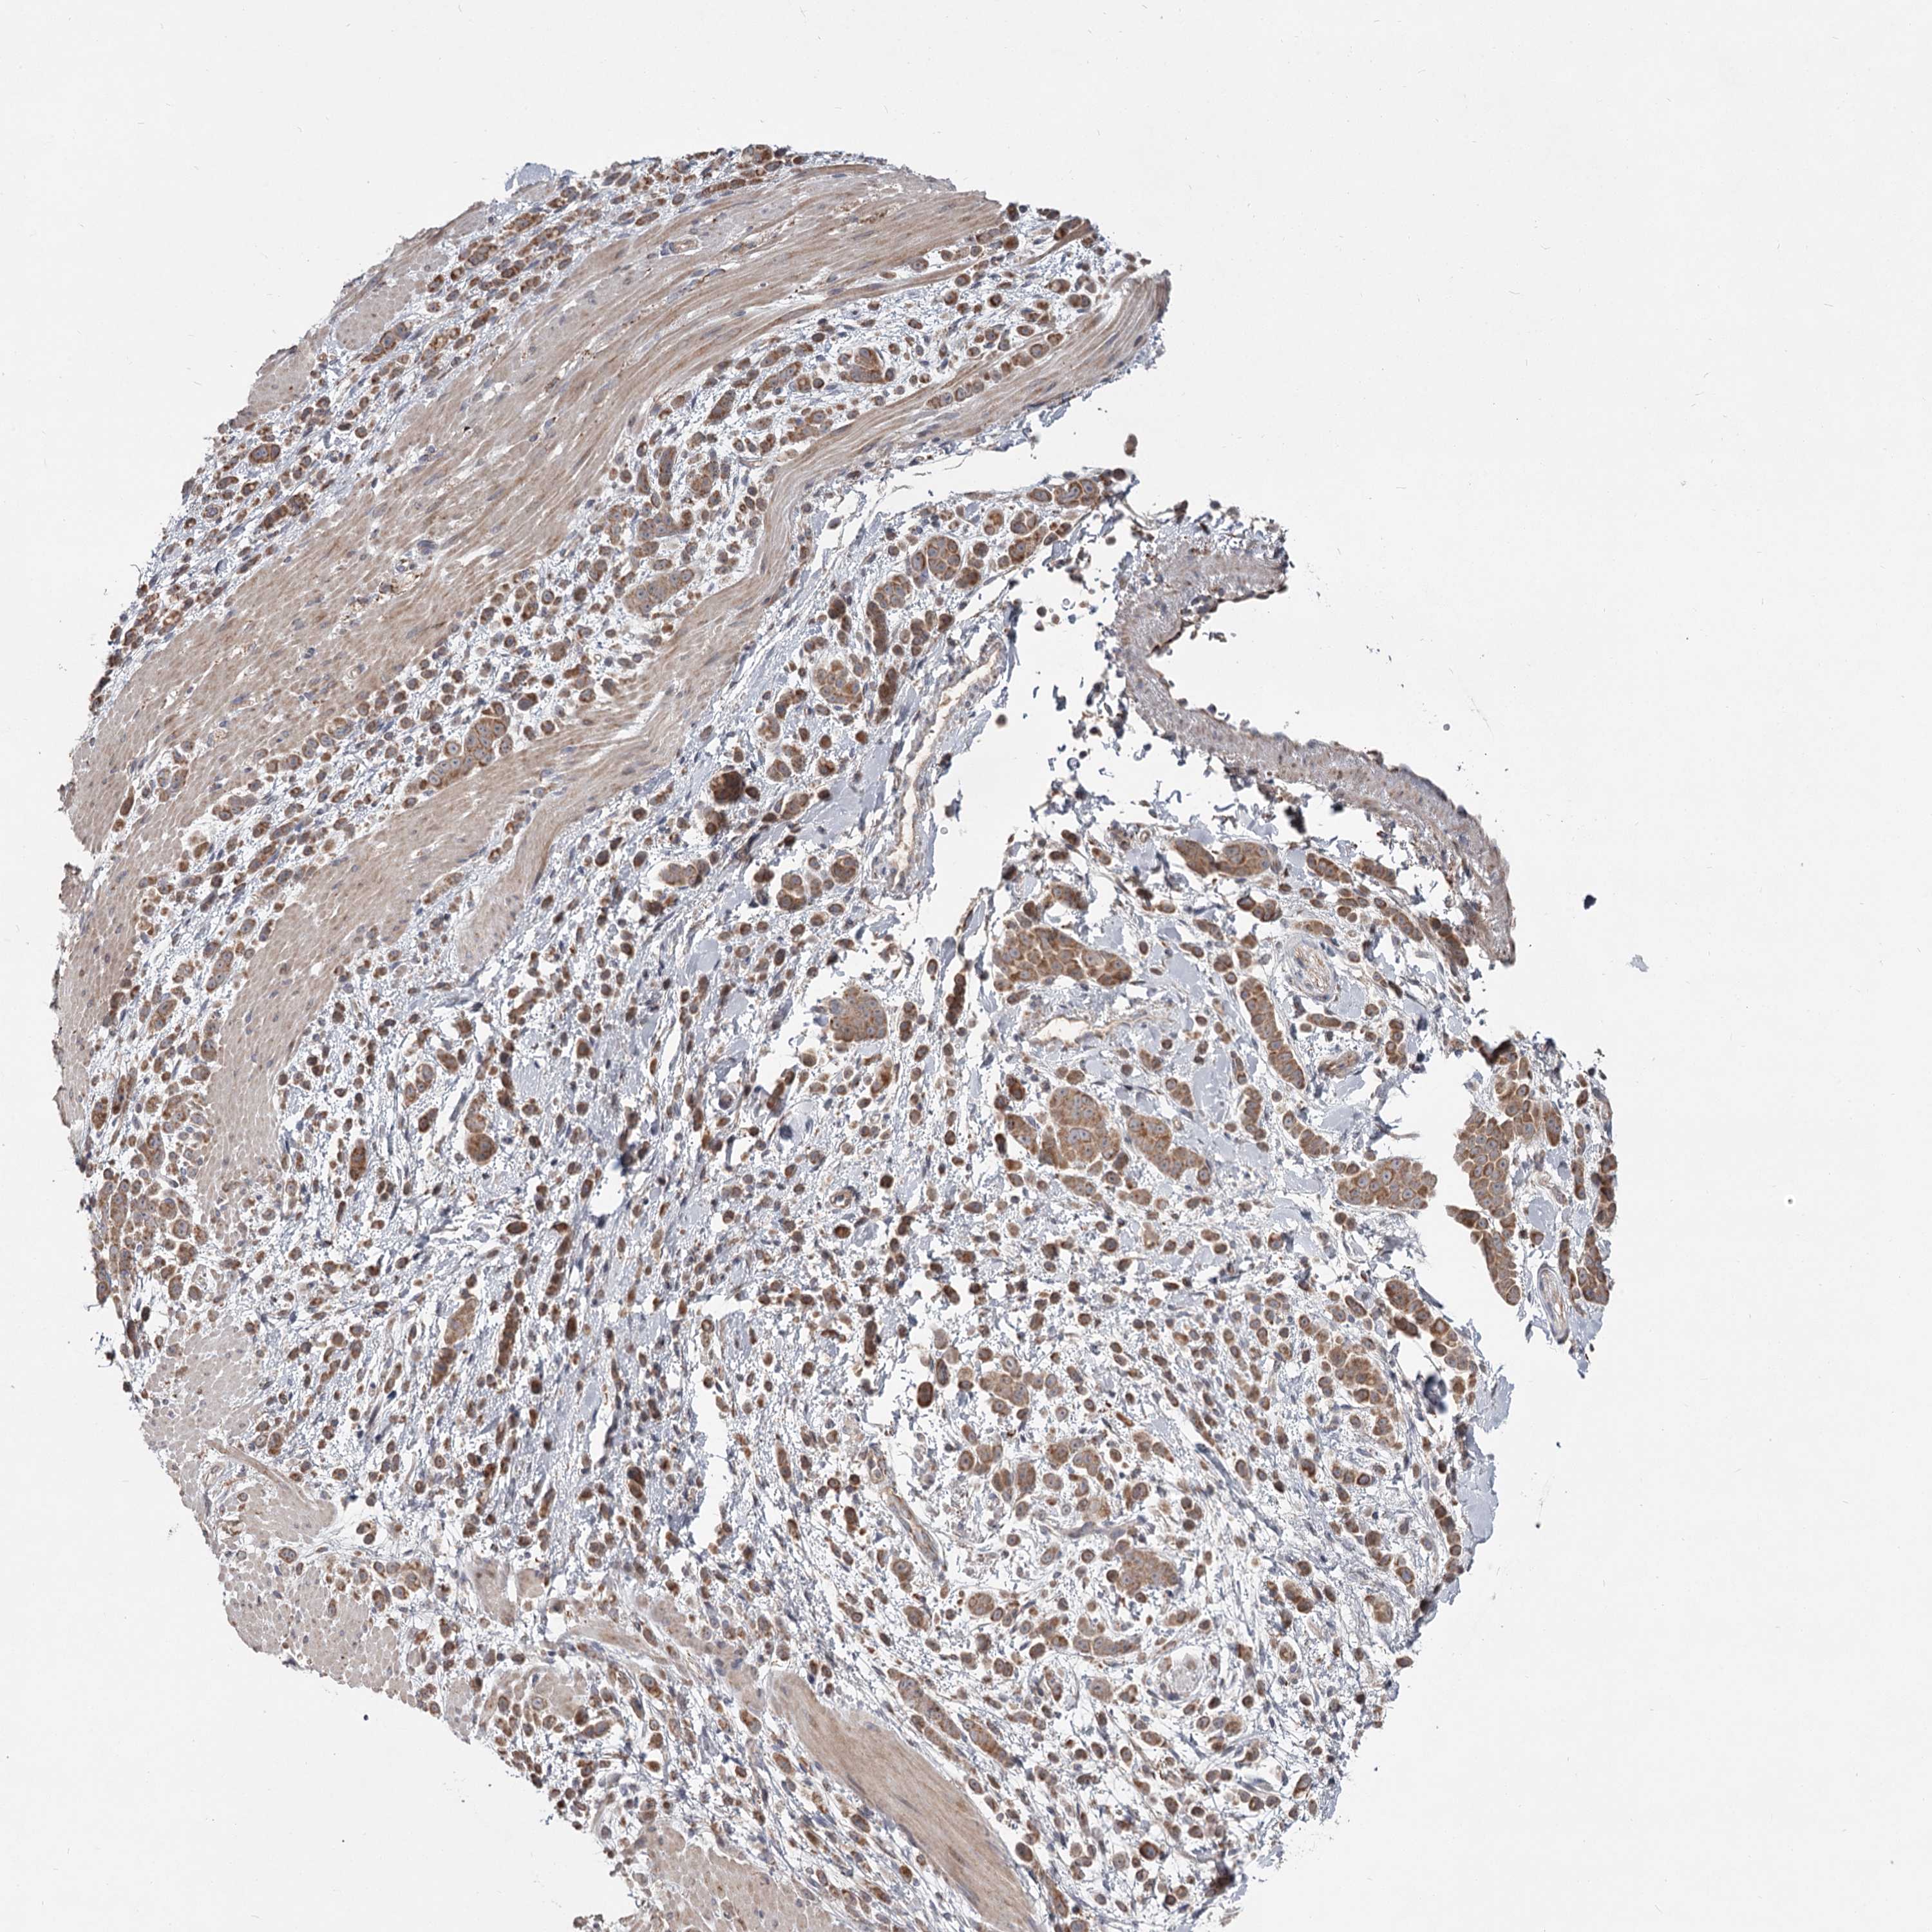

PANCREATIC CANCER - Protein expressioni

A mouse-over function shows sample information and annotation data. Click on an image to view it in a full screen mode. Samples can be filtered based on level of antibody staining by selecting one or several of the following categories: high, medium, low and not detected. The assay and annotation is described here.

Note that samples used for immunohistochemistry by the Human Protein Atlas do not correspond to samples in the TCGA dataset.

Antibody stainingi

Antibody staining in the annotated cell types in the current human tissue is reported as not detected, low, medium, or high, based on conventional immunohistochemistry profiling in selected tissues. This score is based on the combination of the staining intensity and fraction of stained cells.

Each image is clickable and will lead to virtual microscopy that enables deeper exploration of all samples and also displays staining intensity scores, fraction scores and subcellular localization as well as patient and tissue information for each sample.

Antibody HPA037830

Antibody HPA057540

Staining

High

Medium

Low

Not detected

Intensity

Strong

Moderate

Weak

Negative

Quantity

>75%

75%-25%

<25%

None

Location

Nuclear

Cytoplasmic/membranous

Cytoplasmic/membranous,nuclear

Adenocarcinoma, NOS